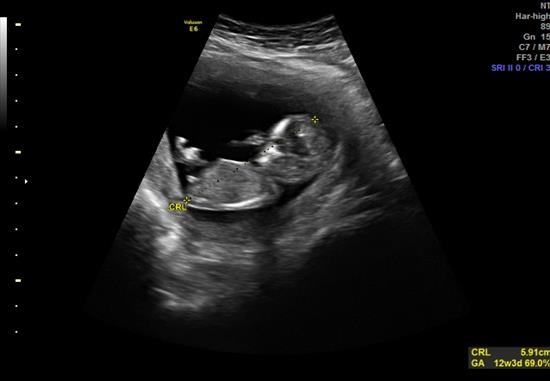

BABY is 12 weeks 4 days...

Attachment 27221

Pink or Blue?

Also -- saw this between the legs, boy parts???